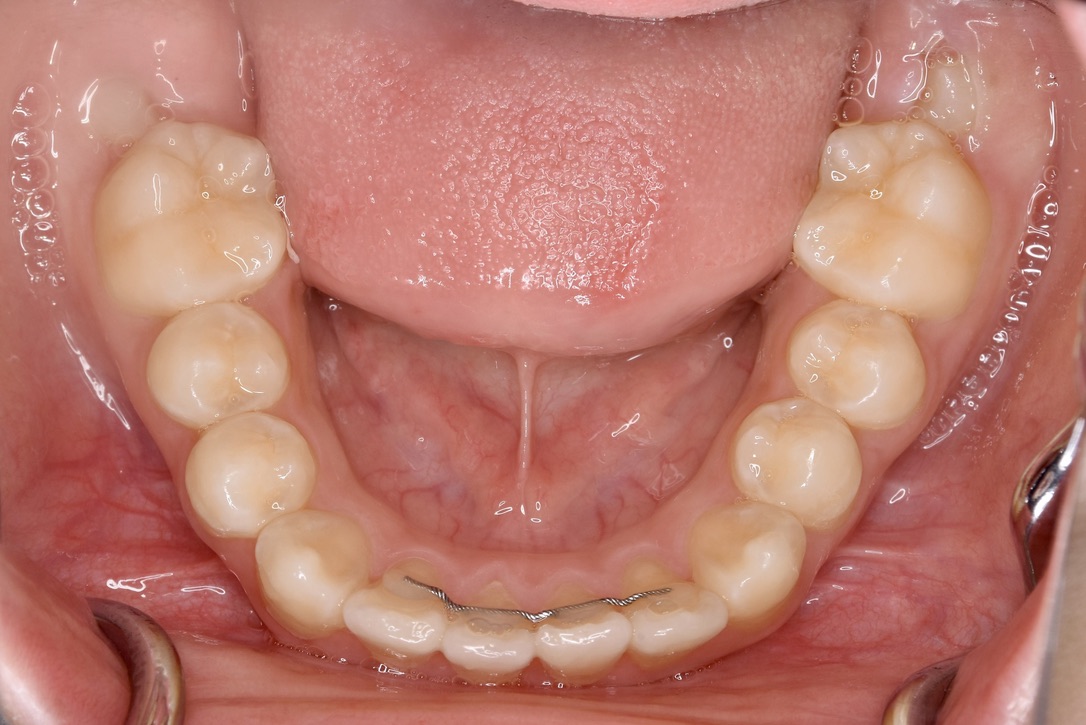

AFTER

主訴 通っている歯医者で矯正した方がいいと言われて気になっている。下の前歯がでこぼこしている。

診断名・主な症状 下顎前歯の叢生を伴う過蓋咬合

年齢 7歳

治療内容 上下の歯並びの幅を拡げつつ、前歯の関係を改善しました。

使用装置 急速拡大装置

リンガルアーチ

機能的矯正装置(マイオブレース)

抜歯部位 抜歯なし

治療期間 2年 + 後戻り止め期間(3年 )

通院回数 20回

費用 50万円程度(税別)  29331

リスク・副作用 痛み、歯肉退縮、歯根吸収、抜歯に伴う出血や腫れが生じることがあります。